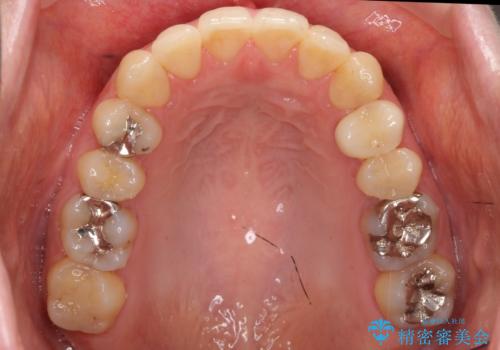

- 前歯2本が後ろに引っ込んでいる状態でした。

マウスピースで歯を抜かずに矯正しました。

かみしめがある方は、奥歯のかみ合わせが弱くなることがマウスピース矯正の欠点ですが、装着時間や時間帯を工夫して奥歯もしっかりかんだ状態で矯正終了をしています。

左上4番は、虫歯治療をして、セラミッククラウンで修復しています。

一般的にマウスピースを装着した状態で歯ぎしりをしてしまうと、奥歯のかみ合わせが弱くなりやすいため、リテーナーはマウスピースではなく、上下の歯が当たるようなホーレータイプが適しています。